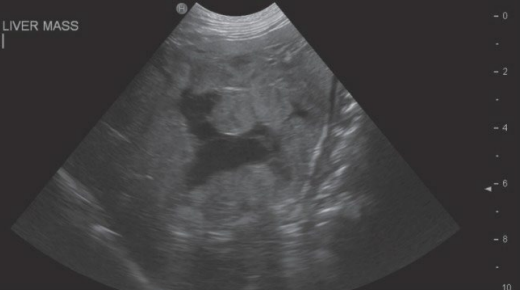

![]() | Thoracic radiographs - pulmonary, mediastinal(์ธ๋ก์นธ) underlying disease ํ์ธ (ex. primary or metastatic neoplasia, granulomatous lesions, heartworm disease; ์๋ฐ์ฑ ๋๋ ์ ์ด์ฑ ์ ์๋ฌผ, ๊ณผ๋ฆฝ์ข ์ฑ ๋ณ๋ณ, ์ฌ์ฅ์ฌ์์ถฉ ๋ฑ) |

![]() | - ํ๋ถ ์งํ ์๋ณ X โ ๋ณต๋ถ ์งํ ์๋ณ (๋ณต๋ถ ์ด์ํ) - ์ผ๋ถ ๊ฒฝ์ฐ ์๋ฐ ๋ณ๋ณ์ ํ์ธํ๊ธฐ ์ํด CT, MRI๊ฐ ํ์ํ ์ ์๋ค. |